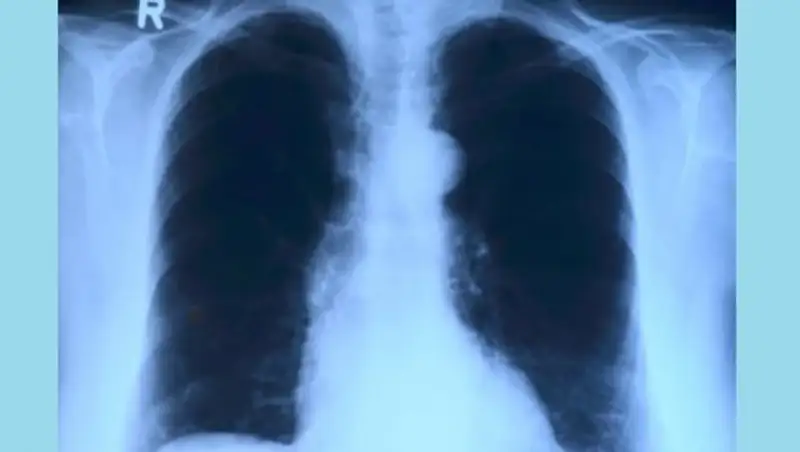

- Самым чувствительным методом выявления рака легкого на данный момент является компьютерная томография. Далее имеется еще такое исследование, как бронхоскопия, биопсия легкого. Также молекулярно-генетическое тестирование, иммуногистохимическое исследование. Это уже диагностика, которая позволяет определить, с каким конкретно видом клеток мы имеем дело. Но первым делом, конечно же, это рентгенография органов грудной клетки. Это для взрослого человека должно быть как само собой разумеющееся.

В завершение хотел бы напомнить, что всем взрослым людям необходимо проходить профилактическую флюорографию ежегодно, а некоторым категориям населения - проходить обзорную рентгенографию. Помните, что если выявить рак легких на ранних стадиях его развития, шансы на успешное излечение от болезни значительно вырастают.